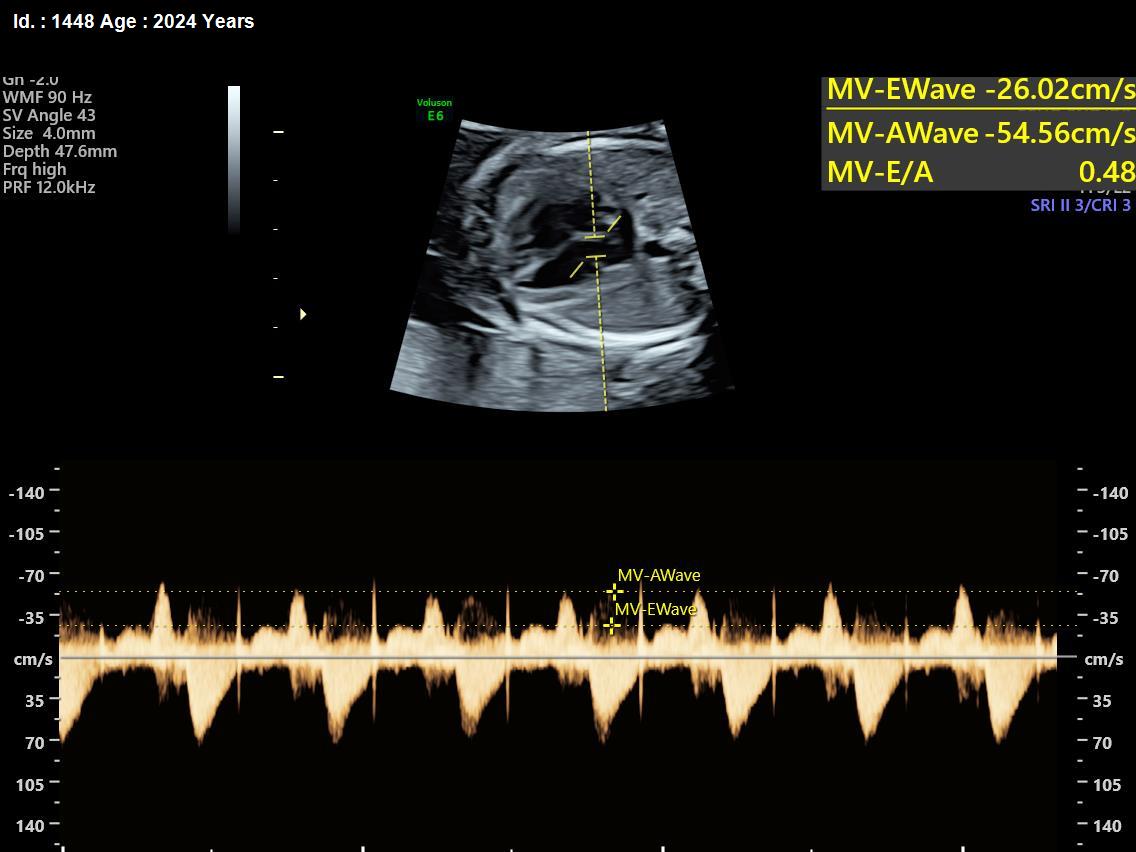

It is a test similar to ultrasound. It allows the doctor to see structure and function of the baby’s heart in detail. It also enables the doctor to see blood flow through fetal heart and cardiac rhythm. The scan is done by a radiologist or a fetal medicine specialist.

A fetal echocardiogram focuses specifically on the fetal heart, providing a detailed examination of its structure and function. In contrast, a standard ultrasound assesses overall fetal development and growth.